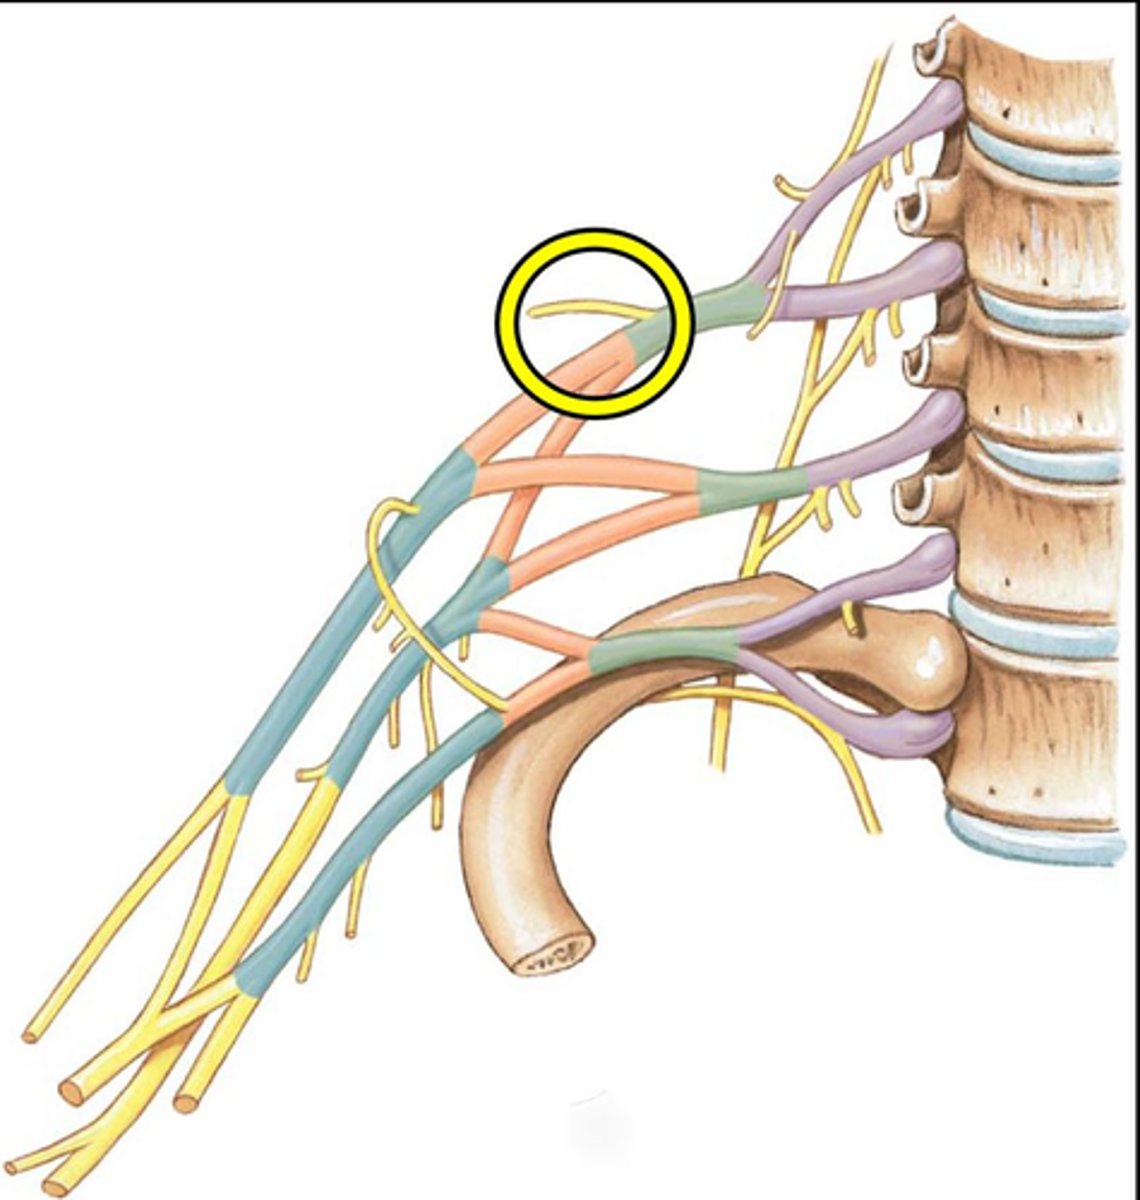

brachial plexus

C5-T1

superior trunk

yellow

middle trunk

orange

inferior trunk

red

lateral cord

pink

medial cord

purple

posterior cord

blue

suprascapular nerve

Branches off the superior trunk